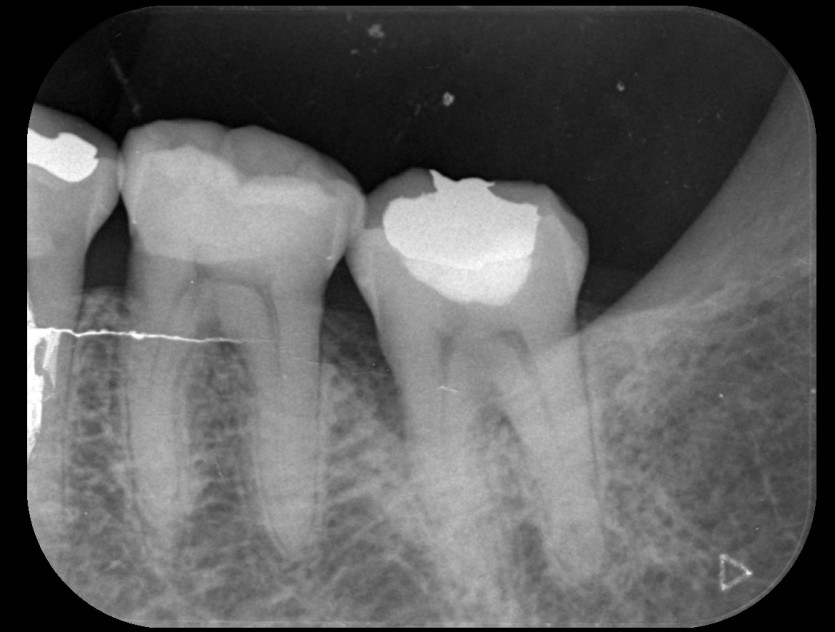

신경치료 사례